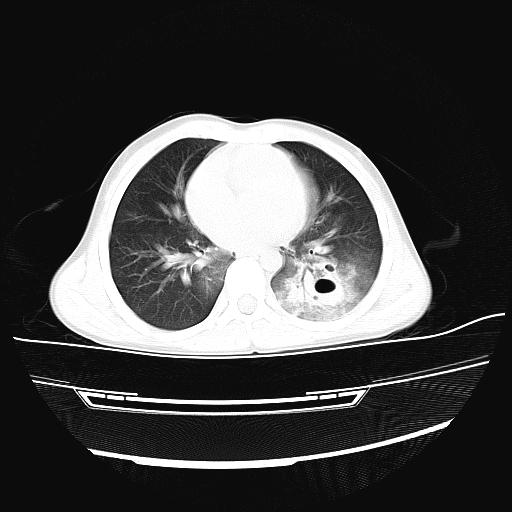

11岁男孩,二楼坠落伤。胸部体症不明星,上腹部痛,腹部ct正常。大家看看,过两天再传复查的片子。

双侧创伤性湿肺,左侧明显并肺大炮。

双侧创伤性湿肺,左侧明显并肺大泡

双侧创伤性湿肺,左侧血肿形成。

双侧创伤性湿肺,左肺挫裂伤,不除外肺囊肿,建议复查.

双侧创伤性湿肺伴左下肺叶创伤性肺气囊形成

双侧创伤性湿肺,左肺挫裂伤(气血囊肿)。

肺挫裂伤并气血囊肿形成

双侧创伤性湿肺伴左下肺撕裂伤并假囊肿形成